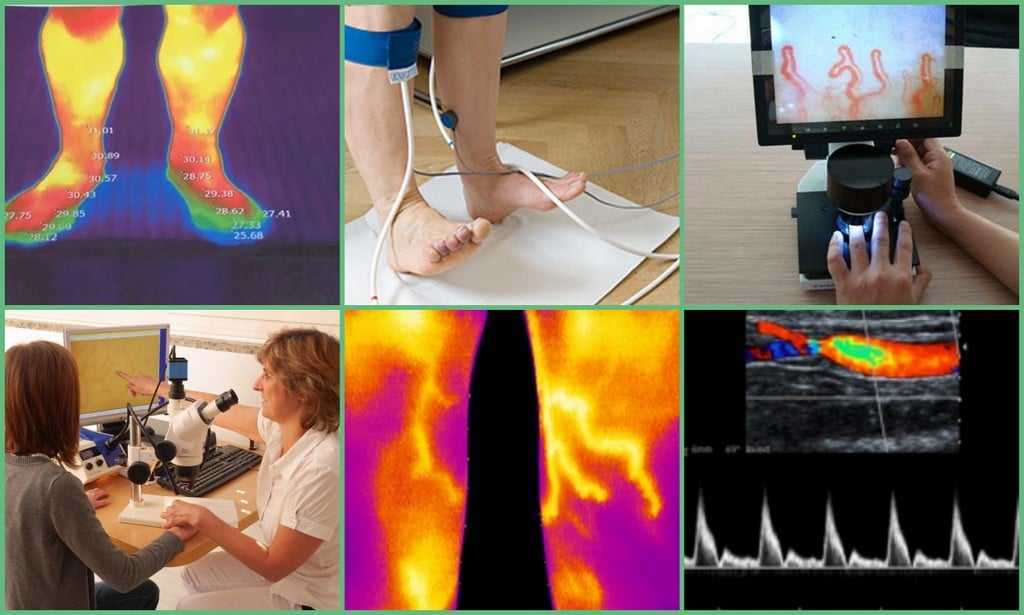

Изображения, связанные с атеросклерозом нижних конечностей и его лечением